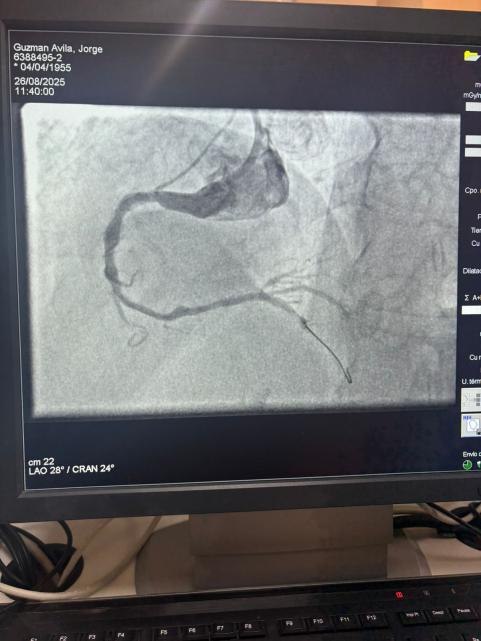

Estamos orgullosos de compartir un caso notable del Hospital Sótero del Río, Chile, donde el Dr. Martín Valdebenito trató con éxito una lesión muy calcificada en la arteria coronaria derecha (primera curva) utilizando nuestro sistema de catéter de dilatación con balón IVL coronario de Vasscrack.

El procedimiento logró resultados sobresalientes, con la región calcificada efectivamente agrietada y el flujo del vaso restaurado. Esto marca otro hito en la expansión del acceso global a soluciones avanzadas para la calcificación coronaria compleja.

La comparación entre las imágenes angiográficas previas y posteriores al procedimiento demuestra claramente el impacto clínico significativo de nuestra tecnología IVL.